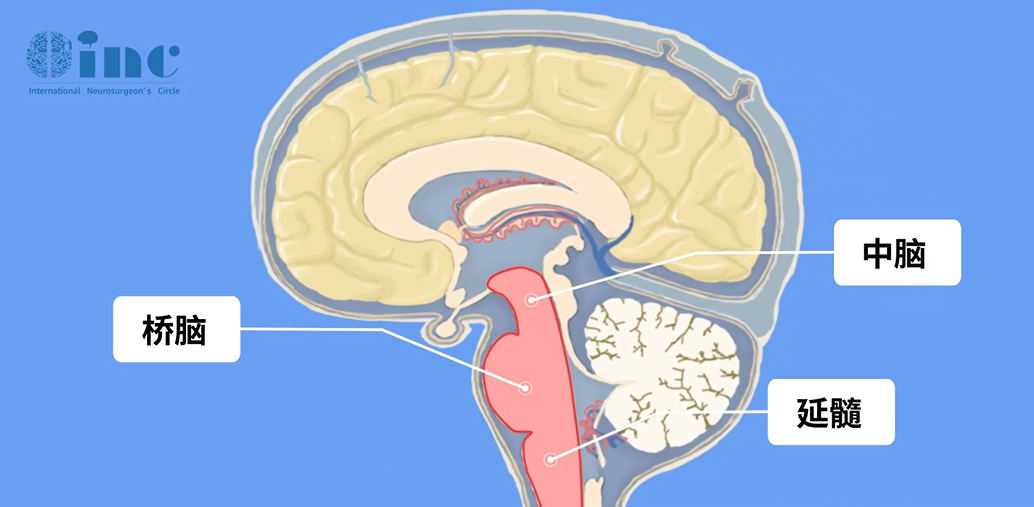

脑桥位于脑干中段,上连中脑,下接延髓,作为大脑、小脑与嵴髓之间的关键枢纽,承担着至关重要的沟通功能。其腹侧面明显隆起,表面沟壑纵横,内部有大量横向神经纤维延伸至小脑,负责协调大脑与小脑之间的信息传递;背侧则参与构成第四脑室底的上部,内含多个颅神经核团(如三叉神经核、展神经核等)以及上下行纤维束,共同调控面部感觉、眼球运动、听觉和平衡等多项生理功能。

此外,脑桥深部还分布有网状结构等生命中枢,对维持意识清醒、睡眠节律和唿吸功能具有重要作用。由于脑桥结构极为复杂,手术操作常需毫米级精度,过去一直被视为“手术禁区”。